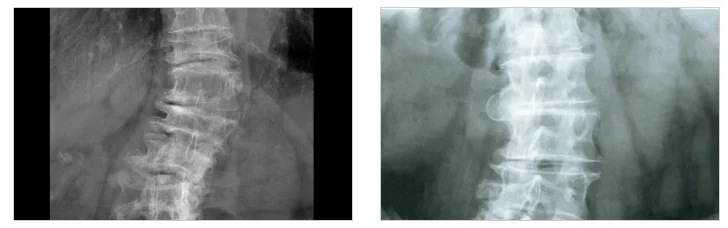

좌골신경통 비수술|허리 척추 X-ray 의료 이미지